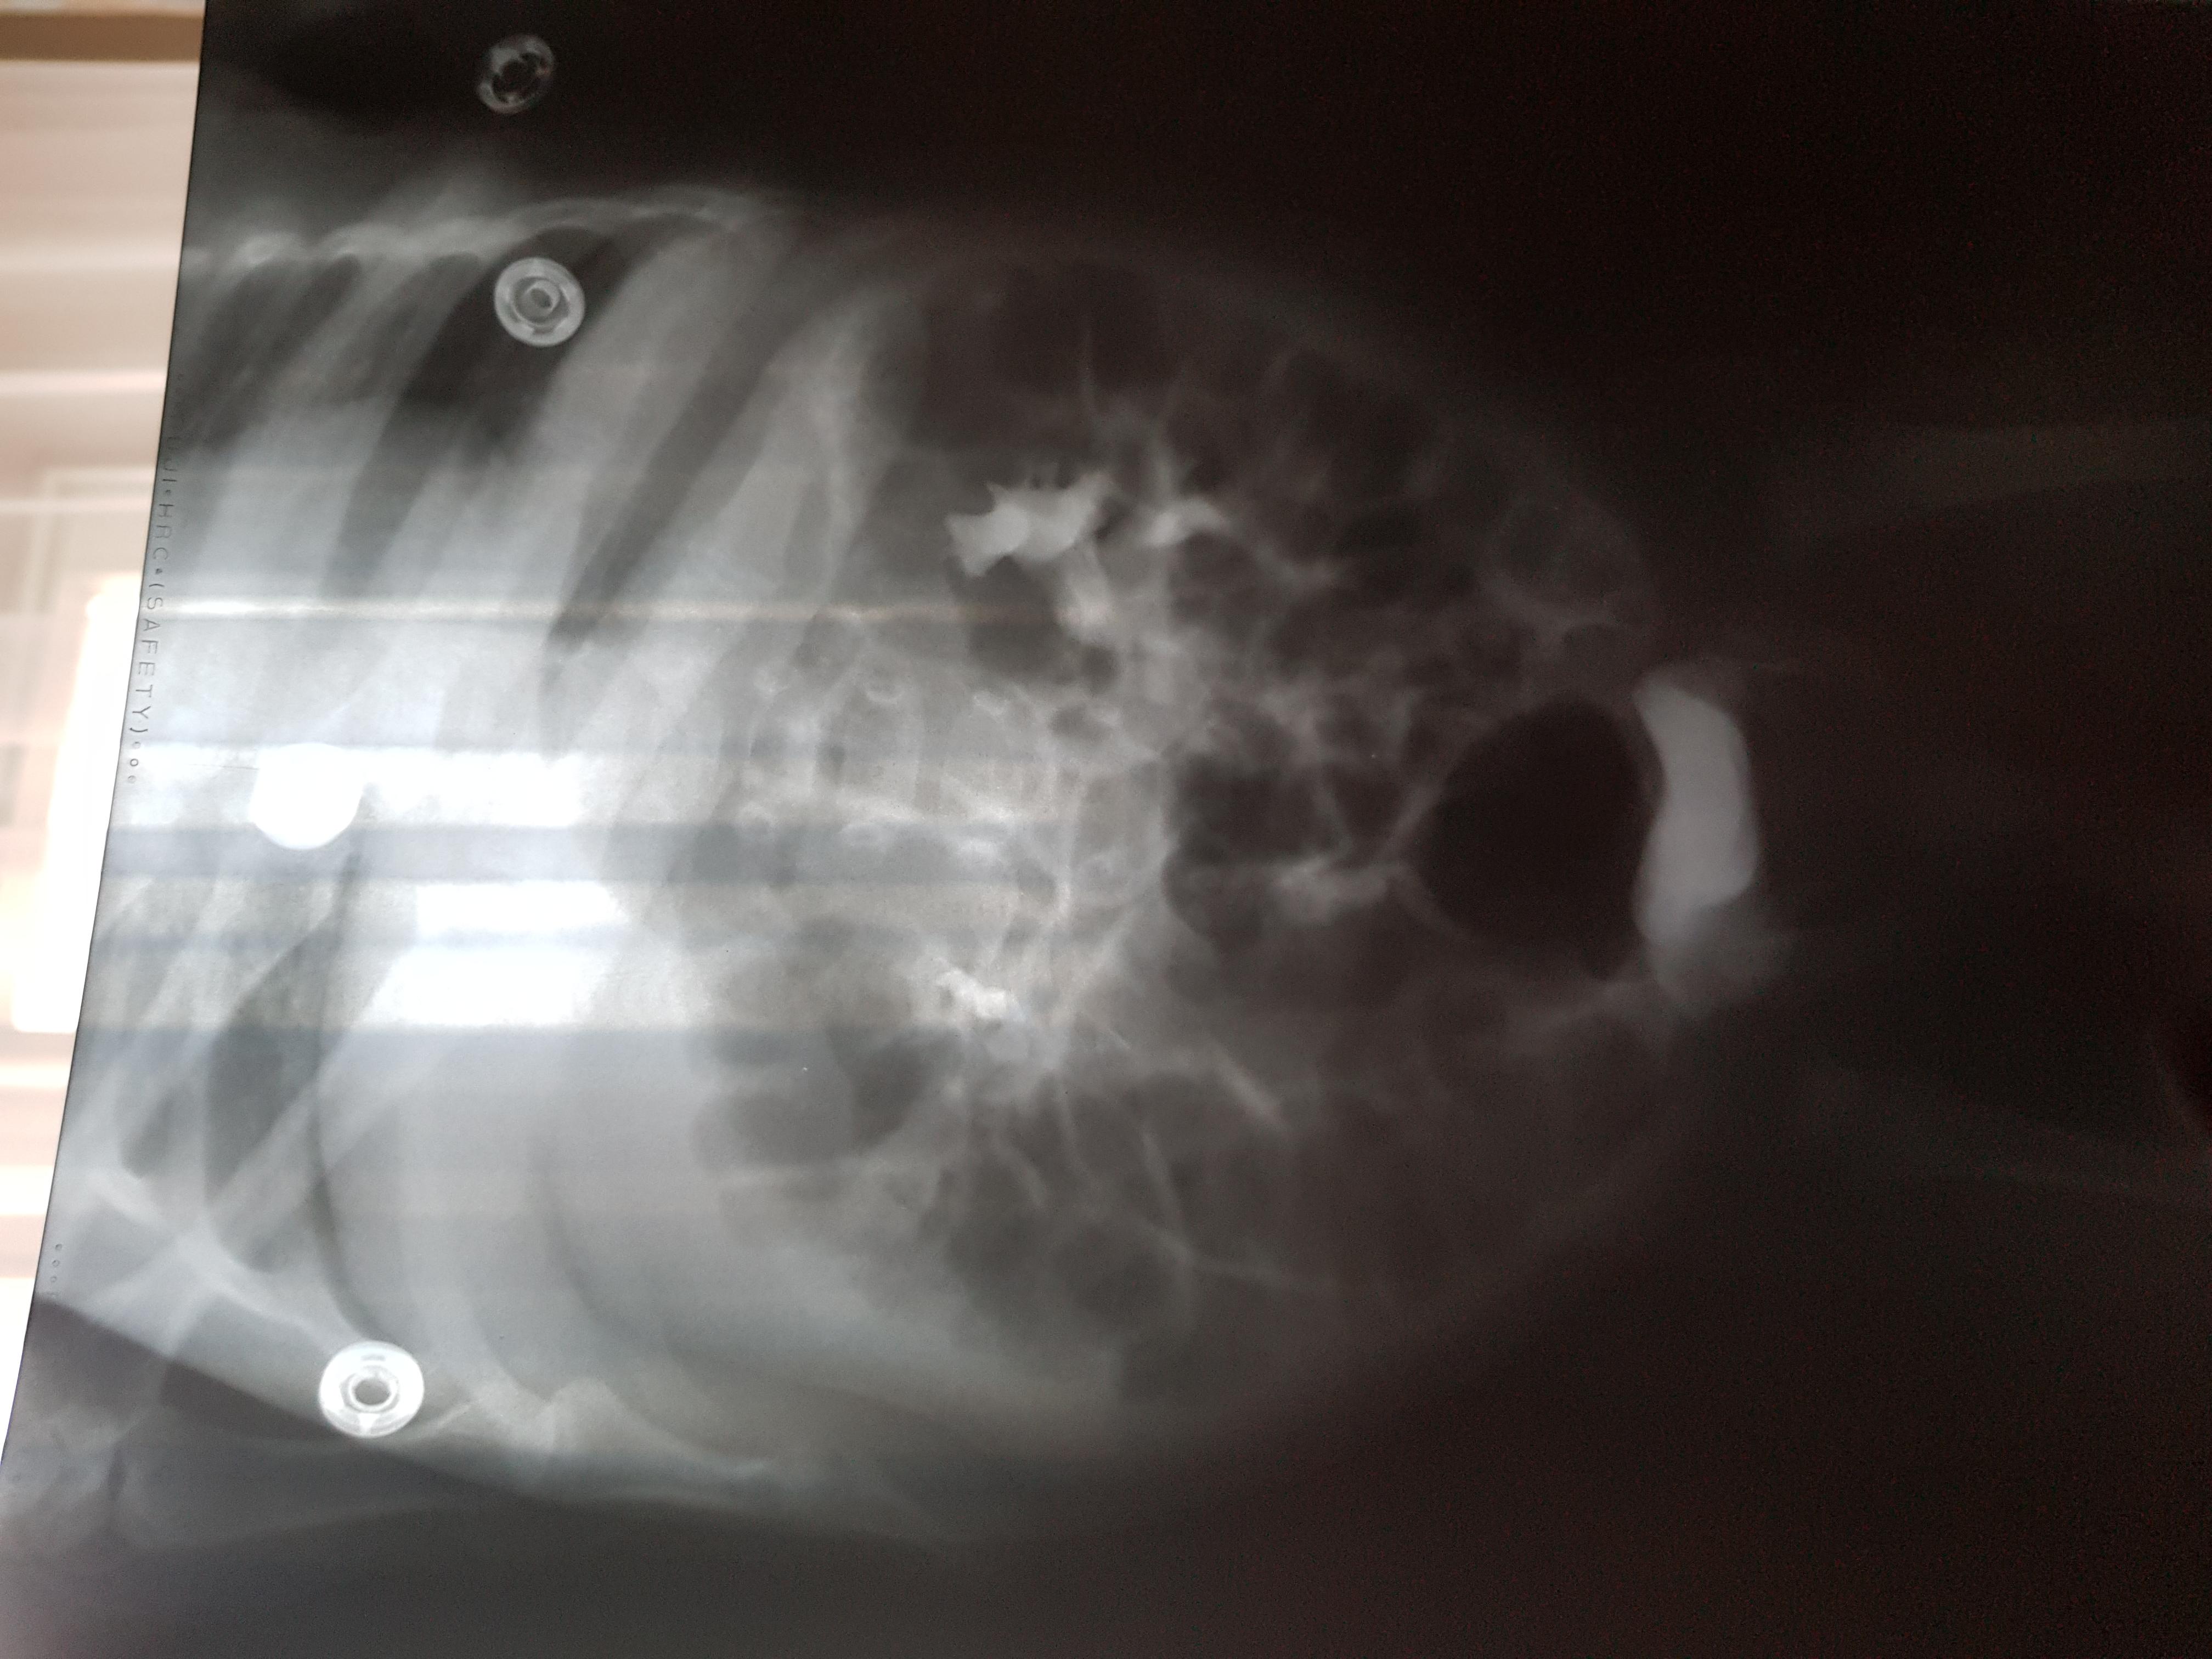

Добрый день! Еще внутриутробно у ребенка обнаружили расширение лоханок.Провели обследование в 1.5 месяца.Поставили диагноз болезнь Ормонда.И назначили консервативное лечение.В 2ух мочеточниках по несколько наростов.рефлюкса не было.Скажиье, возмлжнл что ребенок поосто перерастет?

Болезнь Ормонда (ретроперитонеальный фиброз, забрюшинный фиброз) – хроническое воспаление жировой клетчатки забрюшинного пространства, которое постепенно приводит к компрессии и нарушению проходимости трубчатых структур данного анатомического участка. Чаще всего, в качестве этих тубулярных структур выступают мочеточники.

У меня есть сомнения, что причиной гидронефроза в Вашем случае явилось именно это состояние.

Возможно речь идет о пузырно-мочеточниковом рефлюксе.